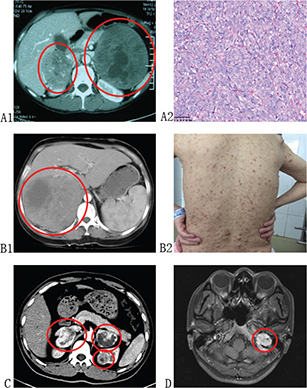

PCC and PGL are considered to be part of clinical syndromes when it comes to hereditary form. An understanding of these syndromes may help to raise awareness of PCC and PGL systematically. The PCC/PGL-related syndromes are summarized in Table 1, and the clinical presentations of PCC/PGL-related syndromes are depicted in Figure 1.

Fig 1

Figure 1. Clinical presentations of PCC/PGL-related syndromes. (A1 and A2): Patient diagnosed with MEN-2 presented with bilateral PCC and MTC. (B1 and B2): Patient diagnosed with NF-1 presented with PCC of right adrenal and multiple neurofibromas on her body. (C): Patient diagnosed with VHL presented with bilateral PCC and left ccRCC. (D): Patient diagnosed with FPGL presented with PGL in her left foramina jugulare, and genetic testing identified germline SDHB mutation of her and her families.